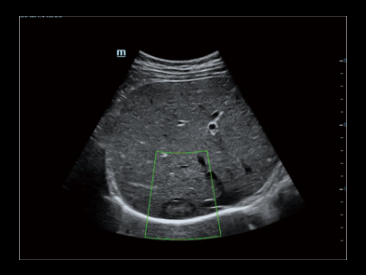

Basado en la potente capacidad de procesamiento de ZST+ , iClear+ proporciona una relaciĂłn se?al / ruido (S/R) mĂĄs alta y menos ruido moteado para una mejor visualizaciĂłn de la imagen.

iClear+ Activado